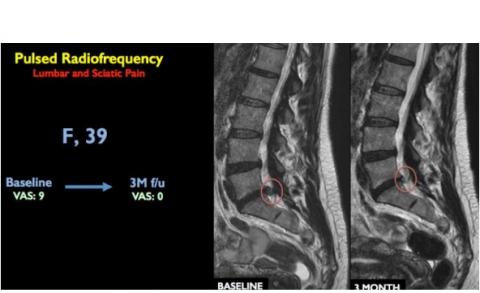

- Suite à ce traitement, l'inflammation et la douleur disparaissent. Avec la relaxation des muscles, la distance entre les vertèbres se rétablit (voir visuel : IRM du rachis lombaire montrant la vertèbre au départ et 3 mois après le traitement).